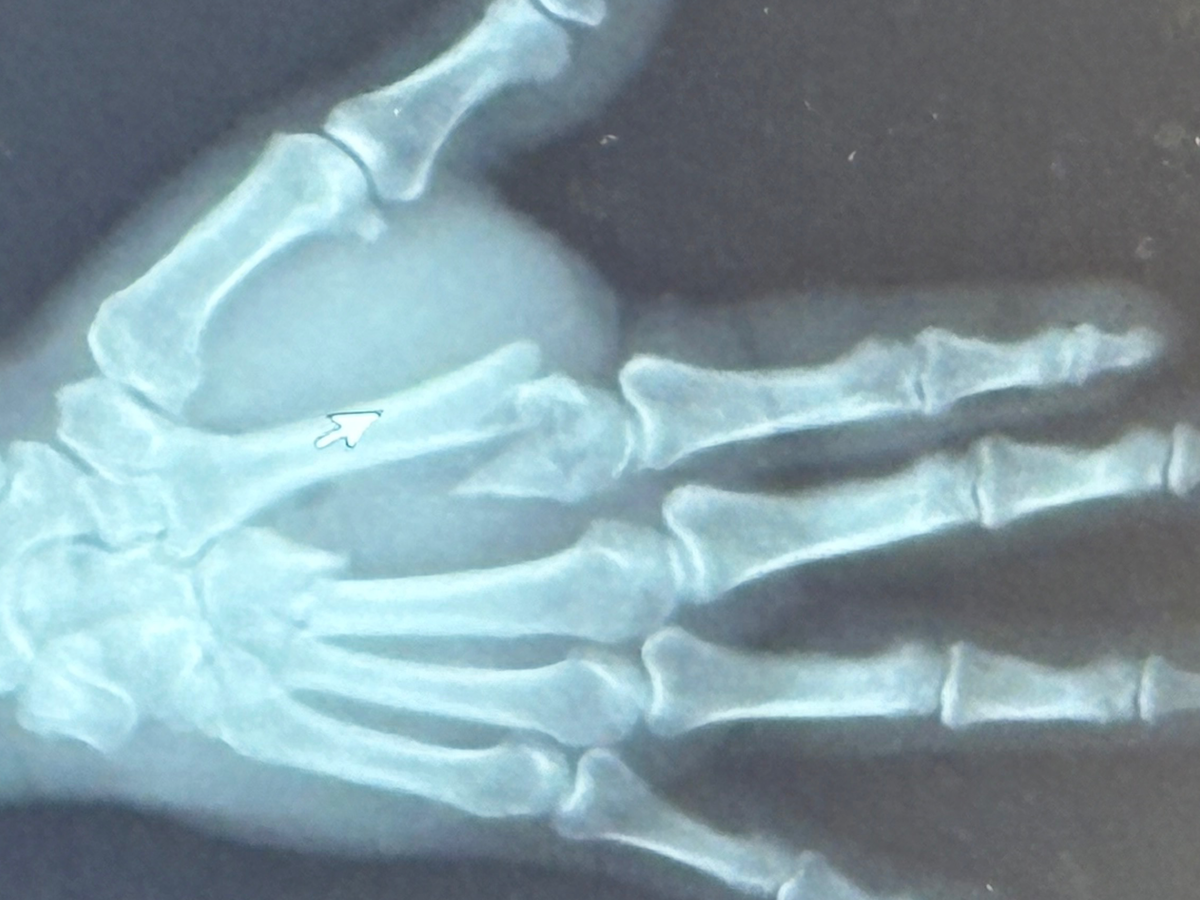

Hello everyone! Not everyone knows this but in September 9, 2025 at about 6pm Chuck had an accident while at work. He was hooking up a grain bagger to a tractor and the hitch of the bagger popped up and smashed Chucks right hand between it and the PTO shaft of the tractor. He had an extensive injury to his hand (which is his dominant hand).

He ended up having basically an emergency surgery that night which went into the next day. He was in surgery for about 2-2 1/2 hours. He now has plates and screws in his hand. Two bones in the top of his hand were affected:

1. The bone leading up to the pointer finger were crushed in 8 places.

2. The bone leading up to the middle finger was broken in 2 places.